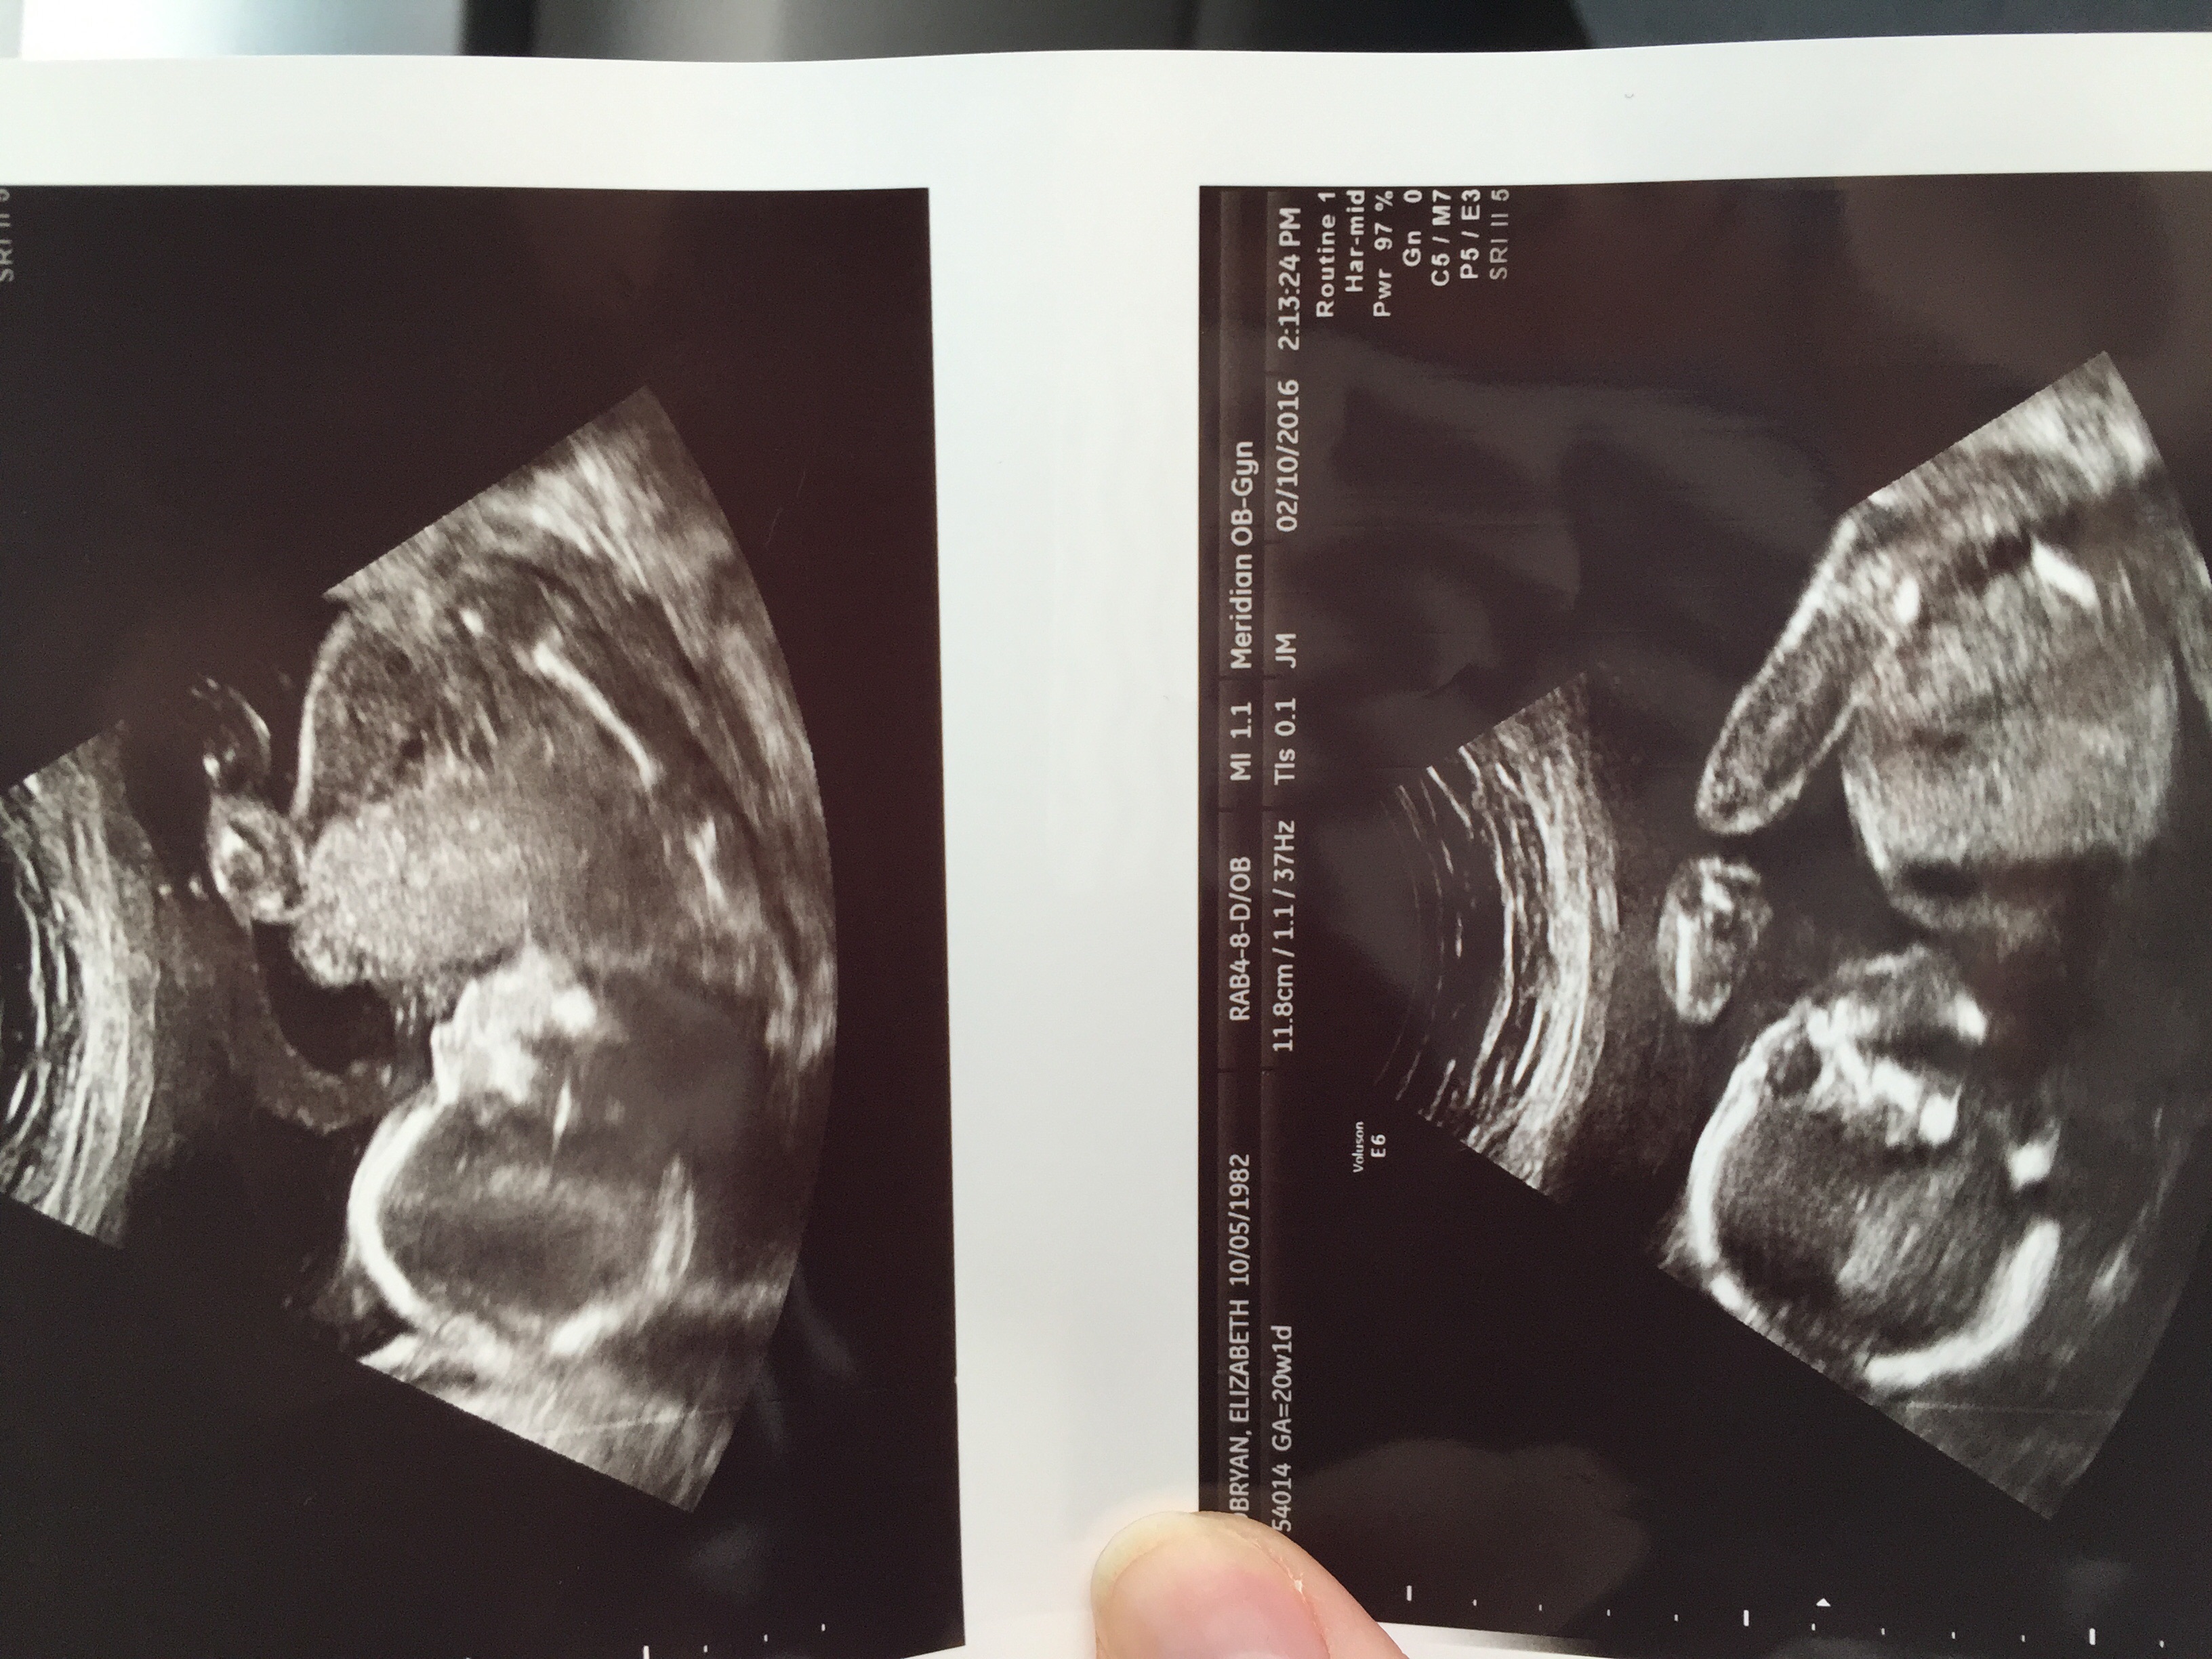

20 weeks ...what do you think??Attachment 29827

1st pic i think boy, cant see any clues on 2nd x

Sorry it might just be me but I'm having trouble working out what I'm actually looking at x

It's not just you mamma. I have no idea either. Are you sure these are potty shots lol

I can't see anything looking like a potty shot here, sorry. What did the tech say? Do you have any 12-14 week nub (full body profile) shots?

Nope she put these in an envelope and sealed it saying these are the potty shots

I only had one initial at 8 weeks and then my 20 week. My husband didn't want to know so asked her to put potty shots in an envelope so I could guesses and that's what she gave me. Darn....

These are the other photos but don't see anything here either